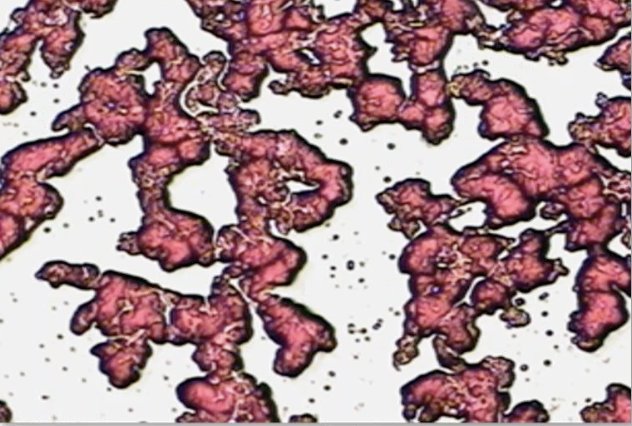

In essence the Dried Blood Analysis test is an evaluation of a patient’s coagulation morphology. There is a very distinct difference between the dried blood sample of a healthy individual and that of a chronically ill patient. The healthy sample is a solid mat of pinkish-red dried blood with a strong, well-interconnected fibrin network.

In the presence of degeneration, toxins and other imbalances, the dried blood sample shows white areas, called polymerized protein puddles (PPPs) and other abnormalities that can be indicative of certain systemic conditions.

A healthy dry blood sample shows a healthy, even red colour, no white open areas and a distinct, interconnected fibrin network.